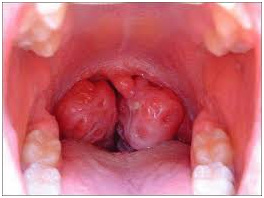

Plazma Yöntemiyle Bademcik Ameliyatı…

Plazma teknolojisi (coblation) kullanılarak yapılan Bademcik küçültülmesi, bademcik alınması ve Geniz eti alınması ameliyatlarında kullanılan ısı diğer yöntemlere göre çok az olduğu için etraf dokulara zarar verme olasılığı çok daha düşük, kanama olasılığı az ve kanamayı kontrol etme olanağı daha güvenli ve iyileşme süreci çok daha kısadır. Bu durum çocukların işlem sonrası kısa sürede normal beslenmeye geçişini sağladığı gibi, okula başlama, arkadaşlarıyla sosyal yaşama dönüş süresini önemli ölçüde kısaltma gibi avantajları da beraberinde getirmektedir.

Prof. Dr. Tuncay Özçelik plazma yöntemiyle bademcik ameliyatı